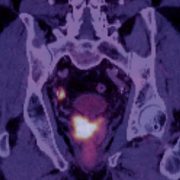

Willkommen zum 16. Petersberger Symposium – dem zentralen Treffpunkt für Expertinnen und Experten der klinischen Radiologie. Unter dem Motto „Radiologie meets Urologie“ widmen wir uns 2026 der Zukunft des Prostata-Screenings: von technischer Innovation über künstliche Intelligenz bis hin zu neuen diagnostischen und therapeutischen Standards.

Moderne Therapie und Rezidiv-Management

• Rezidiv-Erkennung und Nachsorge